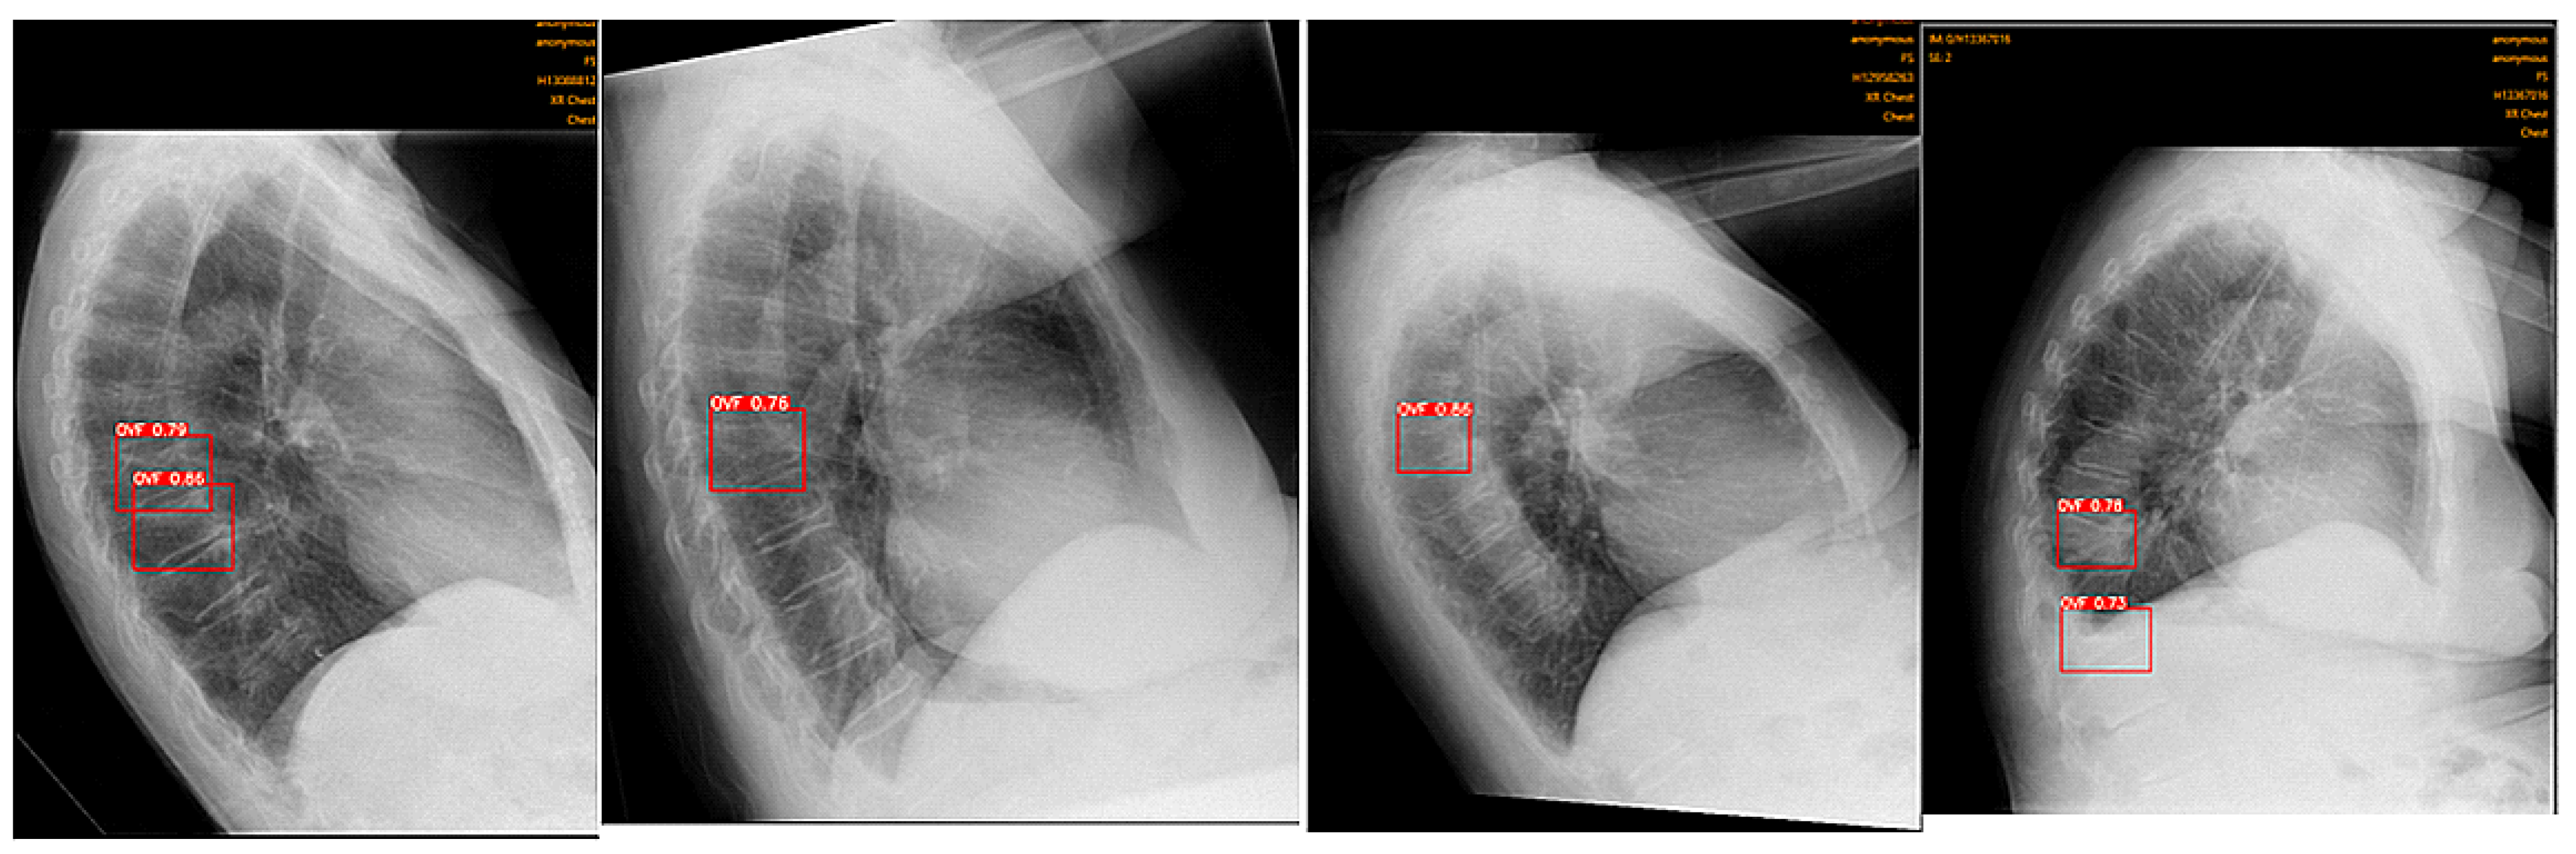

2.2. Image Analysis Using Ofeye 1.0 for Automatic Detection of OVFs

- Xiao, B.H.; Zhu, M.S.; Du, E.Z.; Liu, W.H.; Ma, J.B.; Huang, H.; Gong, J.S.; Diacinti, D.; Zhang, K.; Gao, B.; et al. A software program for automated compressive vertebral fracture detection on elderly women’s lateral chest radiograph: Ofeye 1.0. Quant. Imaging Med. Surg. 2022, 12, 4259–4271. [Google Scholar] [CrossRef]